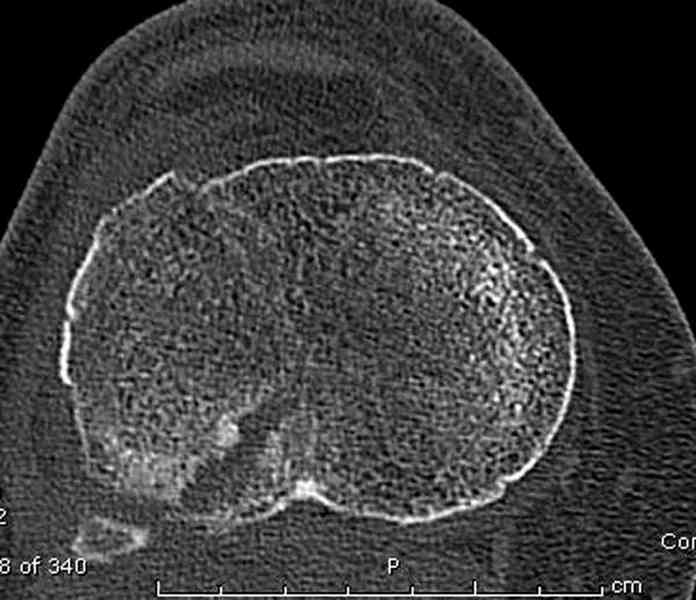

Касаемо перелома мыщелка, лучше сделать СКТ и после определиться с операцией. Фиксировать - проксимальной поддерживающей пластиной. Есть хорошие варианты. Чтож до дистальной части - аппарат кроме стабилизации ничего не даст. Если 6 кг вытяжения не расколотили отломки, то при открытом доступе вся эта мелочь вывалится. По-моема операцию следует рассматривать с позиции подготовки к артродезу (ось выправить, осколки попытаться собрать). Ну и готовить морально пациентку к неработающему голеностопу.

Для внутрисуставных переломов необходимо идеальное сопоставление, а такая задача без КТ срезов усложнится. Только КТ надо делать после дистракции сустава, иначе нельзя получить объективную информацию.